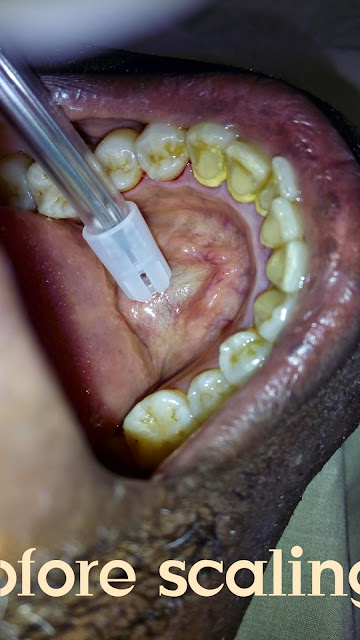

50% Discount Easter Offer on Scaling at Lemacate Global Dental Clinics .

Scaling at Lemacate Global Dental Clinics at 50% Reduced prize as Easter offer from 1/4/2015 to 15/4/2015. Come for your Cleaning Now.